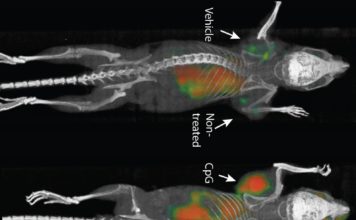

La clave contra la covid podría estar en la nariz

Por Akiko Iwasaki Las vacunas contra la COVID-19 que están autorizadas hoy se desarrollaron a una velocidad sin precedentes y superaron las expectativas sobre su eficacia....